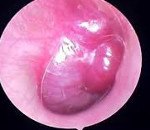

• Физическое обследование. При наблюдении в наружном слуховом канале обнаруживается образование, напоминающее полип, которое имеет контактное кровотечение. Положительный симптом пульсации при введении воронки в ушной канал является показательным. Использование микроотоскопии позволяет выявить контуры параганглиомы в виде бордового пятна за барабанной перепонкой.